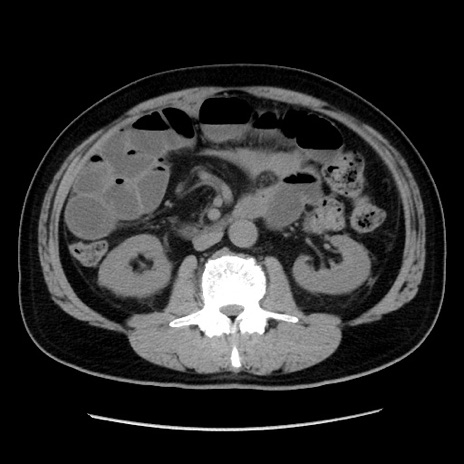

症例16(横断像)

冠状断像

【症例】 70歳代男性

【主訴】 腹痛、嘔吐

【現病歴】 約1ヶ月前より間欠的に腹痛と嘔吐あり、当院消化器内科を受診したところCTで多発する肝臓のLDAを指摘され、精査中であった。以降は消化器症状は安定していたが、2日前より嘔気と腹痛があり、同日より排便・排ガスが消失した。改善認めず、 本日、救急外来を受診した。

【既往歴】 大腸ポリープ切除後。

【身体所見】意識清明・会話良好、BT 36.3℃、BP 127/80mmHg、 P 80bpm、腹部:膨満あり、平坦・軟、上腹部正中および下腹部正中に圧痛あり、反跳痛なし、筋性防御なし。

【データ】WBC 7200、CRP 0.77